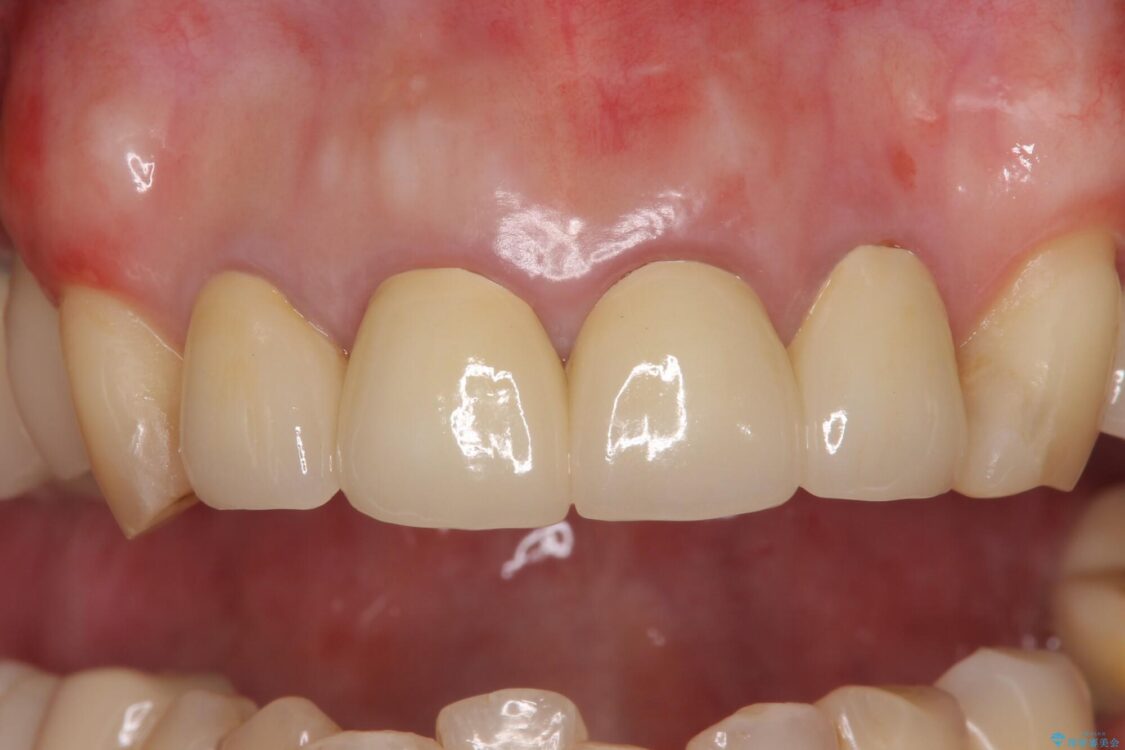

治療後

• 仮歯のまま放置した前歯 オールセラミッククラウンで自然な前歯に 治療後画像